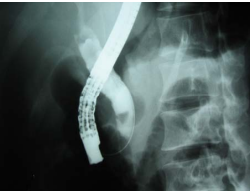

3.3.3. Chụp đường mật ngược dòng qua nội soi dạ dày tá tràng

Là phương pháp dùng ống soi dạ dày tá tràng đưa cathete vào ống mật sau đó bơm thuốc cản quang để chụp hình đường mật giúp chẩn đoán và điều trị. Mc Cune (Mỹ) là người đầu tiên áp dụng phương pháp này. Sau đó đến năm 1970, Oi (Nhật), 1973, Kawai (Nhật), năm 1974, Classen và Demling (Đức) cũng qua nội soi dạ dày cắt cơ vòng Oddi và thực hiện phương pháp này (với tỷ lệ thành công từ 90-94%). Đây là phương pháp rất tốt trong chẩn đoán sỏi đường mật nhưng cũng gây ra biến chứng nhiễm trùng đường mật và viêm tụy cấp với tỷ lệ tử vong 0,5-1%. Vì vậy kỹ thuật này đòi hỏi có nhiều kinh nghiệm [3], [7], [8].

Hình 5. Hình ảnh OMC qua chụp đường mật ngược dòng [5]